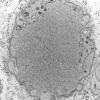

16C1 (Case 16) L PIN nerve_006 - Copy

16C2 (Case 16) L PIN nerve_007 - Copy

16C3 (Case 16) L PIN nerve_022 - Copy

16C4 (Case 16) L PIN nerve_020 - Copy

16C5 (Case 16) L PIN nerve_025 - Copy

16C6 (Case 16) L PIN nerve_027 - Copy